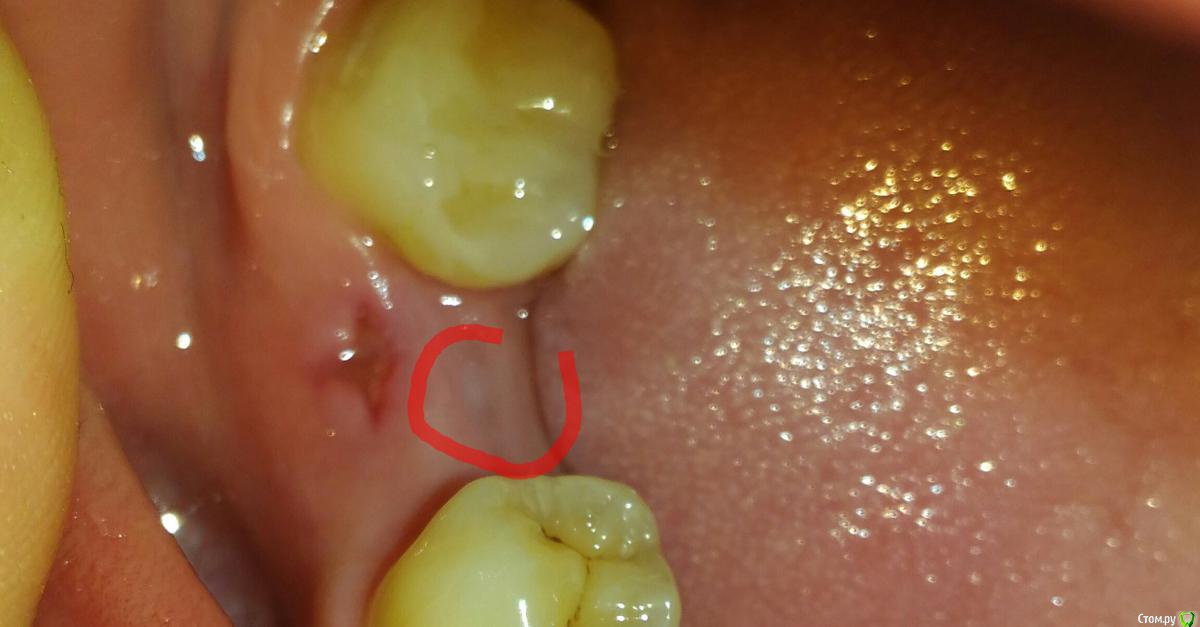

Madira Опубликовано 13 марта, 2016 Поделиться Опубликовано 13 марта, 2016 (изменено) Установила 3 импланта 2 мес назад на месте шестерок. Один сверху, два снизу. И посыпались проблемы. На верхнем обнажилась заглушка, врач сказала, с помощью фдм все исправит. Но это даже не полбеды. С разницей в неделю вскочила сначала шишка на месте одного нижнего импланта, вышло как будто бы немного гноя. Приехала к врачу, вскрыли, почистили. Сказали, на оторжение не похоже. А через неделю белый гнойничок появился на месте второго нижнего импланта и тоже вытекло немного гноя (или сукровицы, не знаю). Болезненных ощущений нет, но были легкие боли первые 3 недели при надавливании. Тогда врач сказала, что заживает,поэтому болит. Сейчас ничего не болит. Очень переживаю, т.к. годами копила на эту имплантацию, и столько возникло проблем, а денег на новые импланты не предвидется еще долго. Врачу уже не очень доверяю,т.к. она даже снимки отказалась сейчас делать, якобы не показетельно, будет делать перед установкой фдм...но меня очень пугают эти гнойнички. Они похожи на свищи. Выкладываю фото, надеюсь хоть что-то оно разьяснит. Спасибо! Изменено 13 марта, 2016 пользователем Madira Ссылка на комментарий

red_butler Опубликовано 16 марта, 2016 Поделиться Опубликовано 16 марта, 2016 Частично поправить ситуацию можно пластикой мягких тканей, об этом я бы вел речь, применительно к импланту в позиции 3.6Еще раз спрашиваю, ортопеду показывались? Ссылка на комментарий

Madira Опубликовано 16 марта, 2016 Автор Поделиться Опубликовано 16 марта, 2016 Спасибо. Доктор посмотрела, сказала, что да, есть воспалительеый процесс. Плохо, но не смертельно. Продолжает настаивать что импланты были докручены, даже чуть вглубь в кость заходили. Предложила пообщаться вместе с глав.клиникой, если я ей не доверяю. С ортопедом тоже на след.неделе только удастся пообщаться.Установила формирователи, уверила что дальше резорбция не пойдет. И сейчас она в пределах физиологической нормы.Что такое случается, но обычно развивается в течение первых лет, а не месяцев. К слову, импланты, по ее словам, прижились, никто их выпиливать с костью конечно уже не станет.(( Ссылка на комментарий